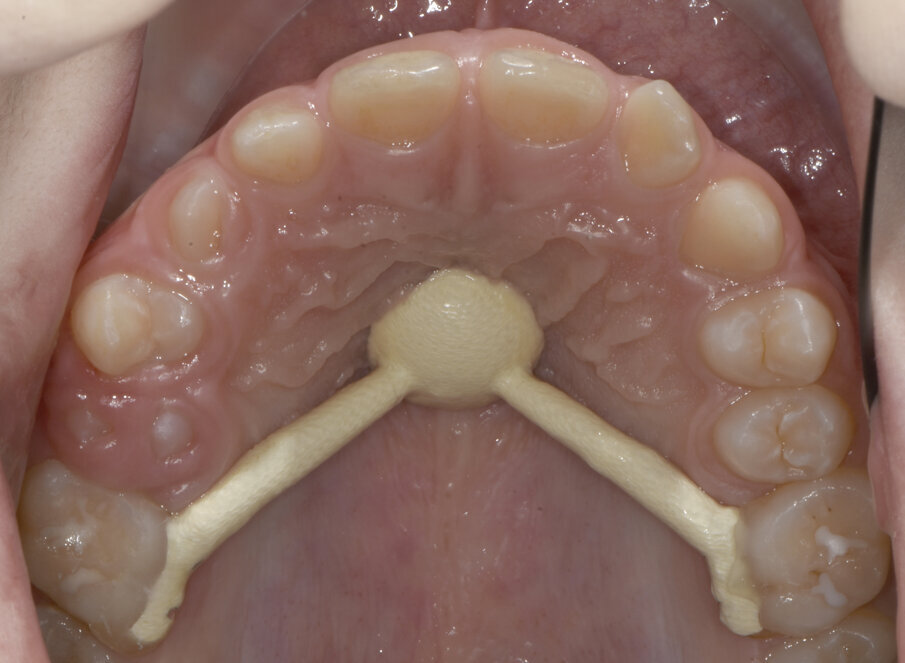

Dopo aver rilevato delle impronte con polivinilsilossano per realizzare un espansore del palato, si esegue l’espansione rapida del mascellare (Figg. 5, 6) superiore con il dispositivo cementato sui secondi molari decidui (5.5-6.5). Al termine dell’espansione, sono rilevate delle nuove impronte con polivinilsilossano per realizzare una barra palatale (Fig. 6) ancorata sui primi molari permanenti (1.6-2.6); viene eseguito un protocollo di estrazioni anticipate dei primi molari decidui e dei canini decidui (Figg. 7-9).

Fig. 7_Barra palatale, exo “D” ed eruzione 1.4-2.4.